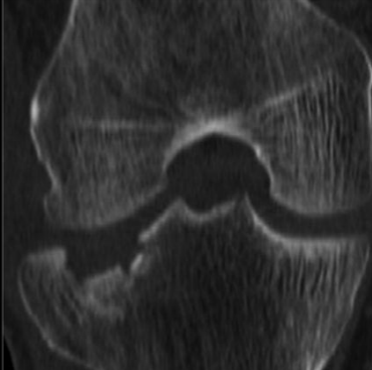

Uso de RM en fracturas

Lesiones ligamentaria o tendinosa

Rx ocultas